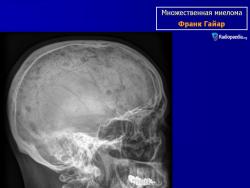

Рентгенологические проявления миеломы бывают классическими с четкими литическими очагами, окруженными ободком склероза, также характерен остеопороз различной степени выраженности, что часто приводит к патологическим переломам. В 25% случаев очаг поражения не выявляется при обычной рентгенографии, при помощи КТ и МРТ выявляют маленькие очаги поражения.

МИЕЛОМА, МНОЖЕСТВЕННАЯ МИЕЛОМА, МИЕЛОМНАЯ БОЛЕЗНЬ, СЕКРЕТИРУЮЩАЯ ЛИМФОМА, ПЛАЗМАЦИТОМА, БОЛЕЗНЬ РУСТИЦКОГО и т.д. – все это синонимы одного заболевания, которое обусловлено неконтролируемым ростом плазматических клеток, продуцируемым костным мозгом. Плазматические клетки, в свою очередь, являются конечной стадией дифференциации В-лимфоцитов – основного звена клеточно-гуморального иммунитета, основная функция которых – продукция иммунных белков – иммуноглобулинов IgG, IgA, IgM, IgE, IgD, участвующих в гуморальном иммунитете. Поэтому в норме костный мозг всегда содержит некоторое количество плазматических клеток. Однако, в случае их неконтролируемого роста увеличение количества плазматических клеток приводит к их сосредоточению в виде плазмацитомы в костном мозге, особенно в позвоночном столбе, тазовых костях, ребрах, плоских костях черепа, головках тазобедренных суставов, в результате чего нормальная костная ткань и костный мозг разрушаются. Очаги деструкции видны при рентгеновском исследовании, но, к сожалению, разрешающая способность рентгена позволяет выявить разрежение костной ткани, если порядка 30% ее уже разрушено. Миеломные клетки продуцируют иммуноглобулин одного вида (моноклональный), который при специфическом электрофоретическом исследовании сыворотки крови и мочи проявляется пиком, называемым М-градиентом, где М - означает моноклональный или миеломный. Отсюда происходит название болезни – миелома. Моноклональные белки (протеины), продуцируемые миеломными клетками, имеют измененную структуру, не выполняют функций иммунитета и называются «парапротеинами». Иногда они теряют какую-то свою часть и могут продуцироваться только моноклональные легкие цепи (белок Бенс-Джонса), или моноклональные тяжелые цепи.